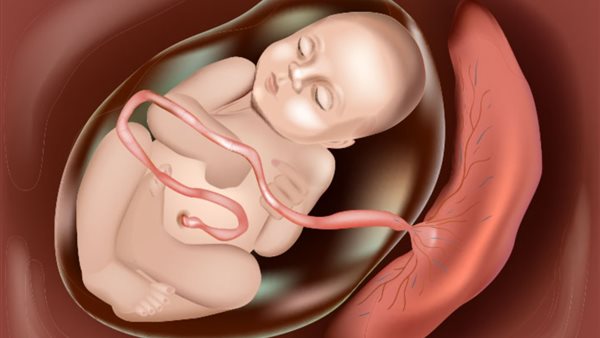

حتى الآن، لم يكن من الواضح كيف يتمكن الفيروس من عبور المشيمة، التي تغذي الجنين النامي وتشكل حاجزًا قويًا ضد الميكروبات والمواد الكيميائية التي يمكن أن تضر بالجنين.

وأضافت: "إن فهم كيفية انتشار فيروس زيكا عبر المشيمة البشرية ووصوله إلى الجنين أمر بالغ الأهمية لمنع أو السيطرة على هذه الحالة المدمرة".